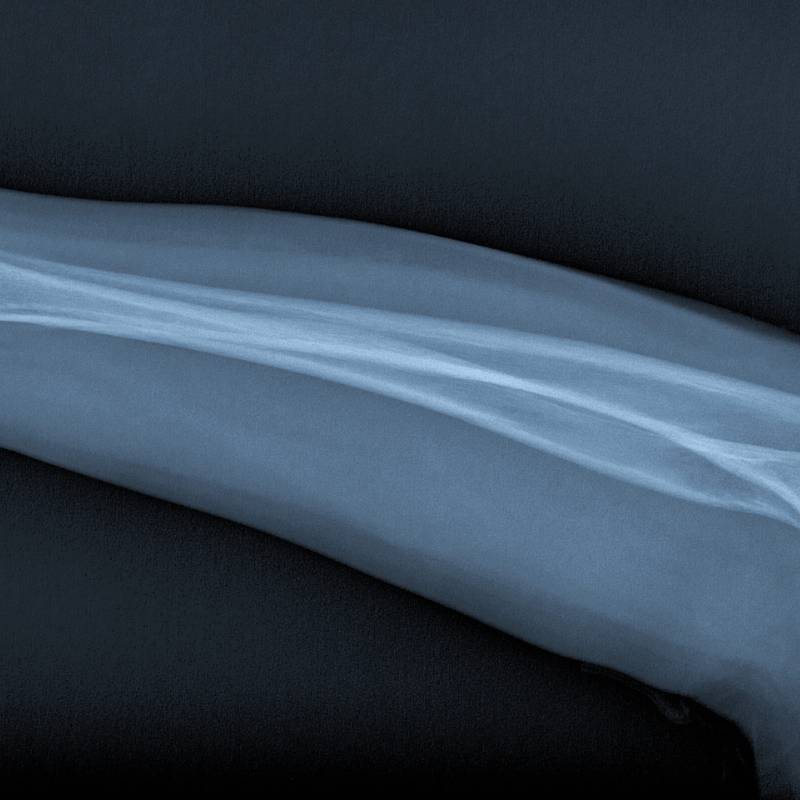

Pemeriksaan sinar-X pada tulang lengan bawah.